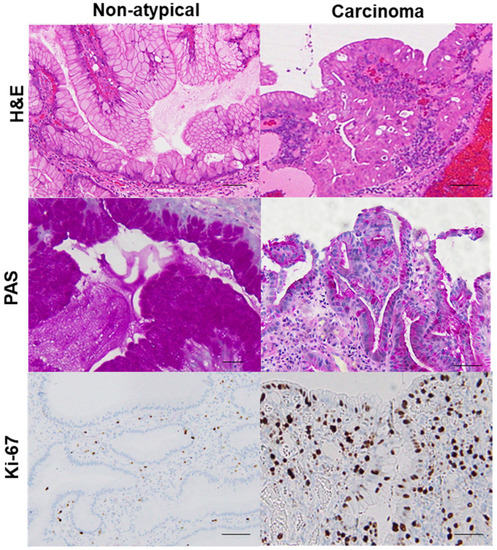

| PAS staining (3) | 2.0 ± 0.1 | 1.4 ± 0.5 | 0.8 ± 0.3 | 0.6 ± 0.2 | <0.0001 |

| Ki-67 index (%) (4) | 26 ± 13 | 52 ± 23 | 74 ± 18 | 86 ± 10 | <0.0001 |